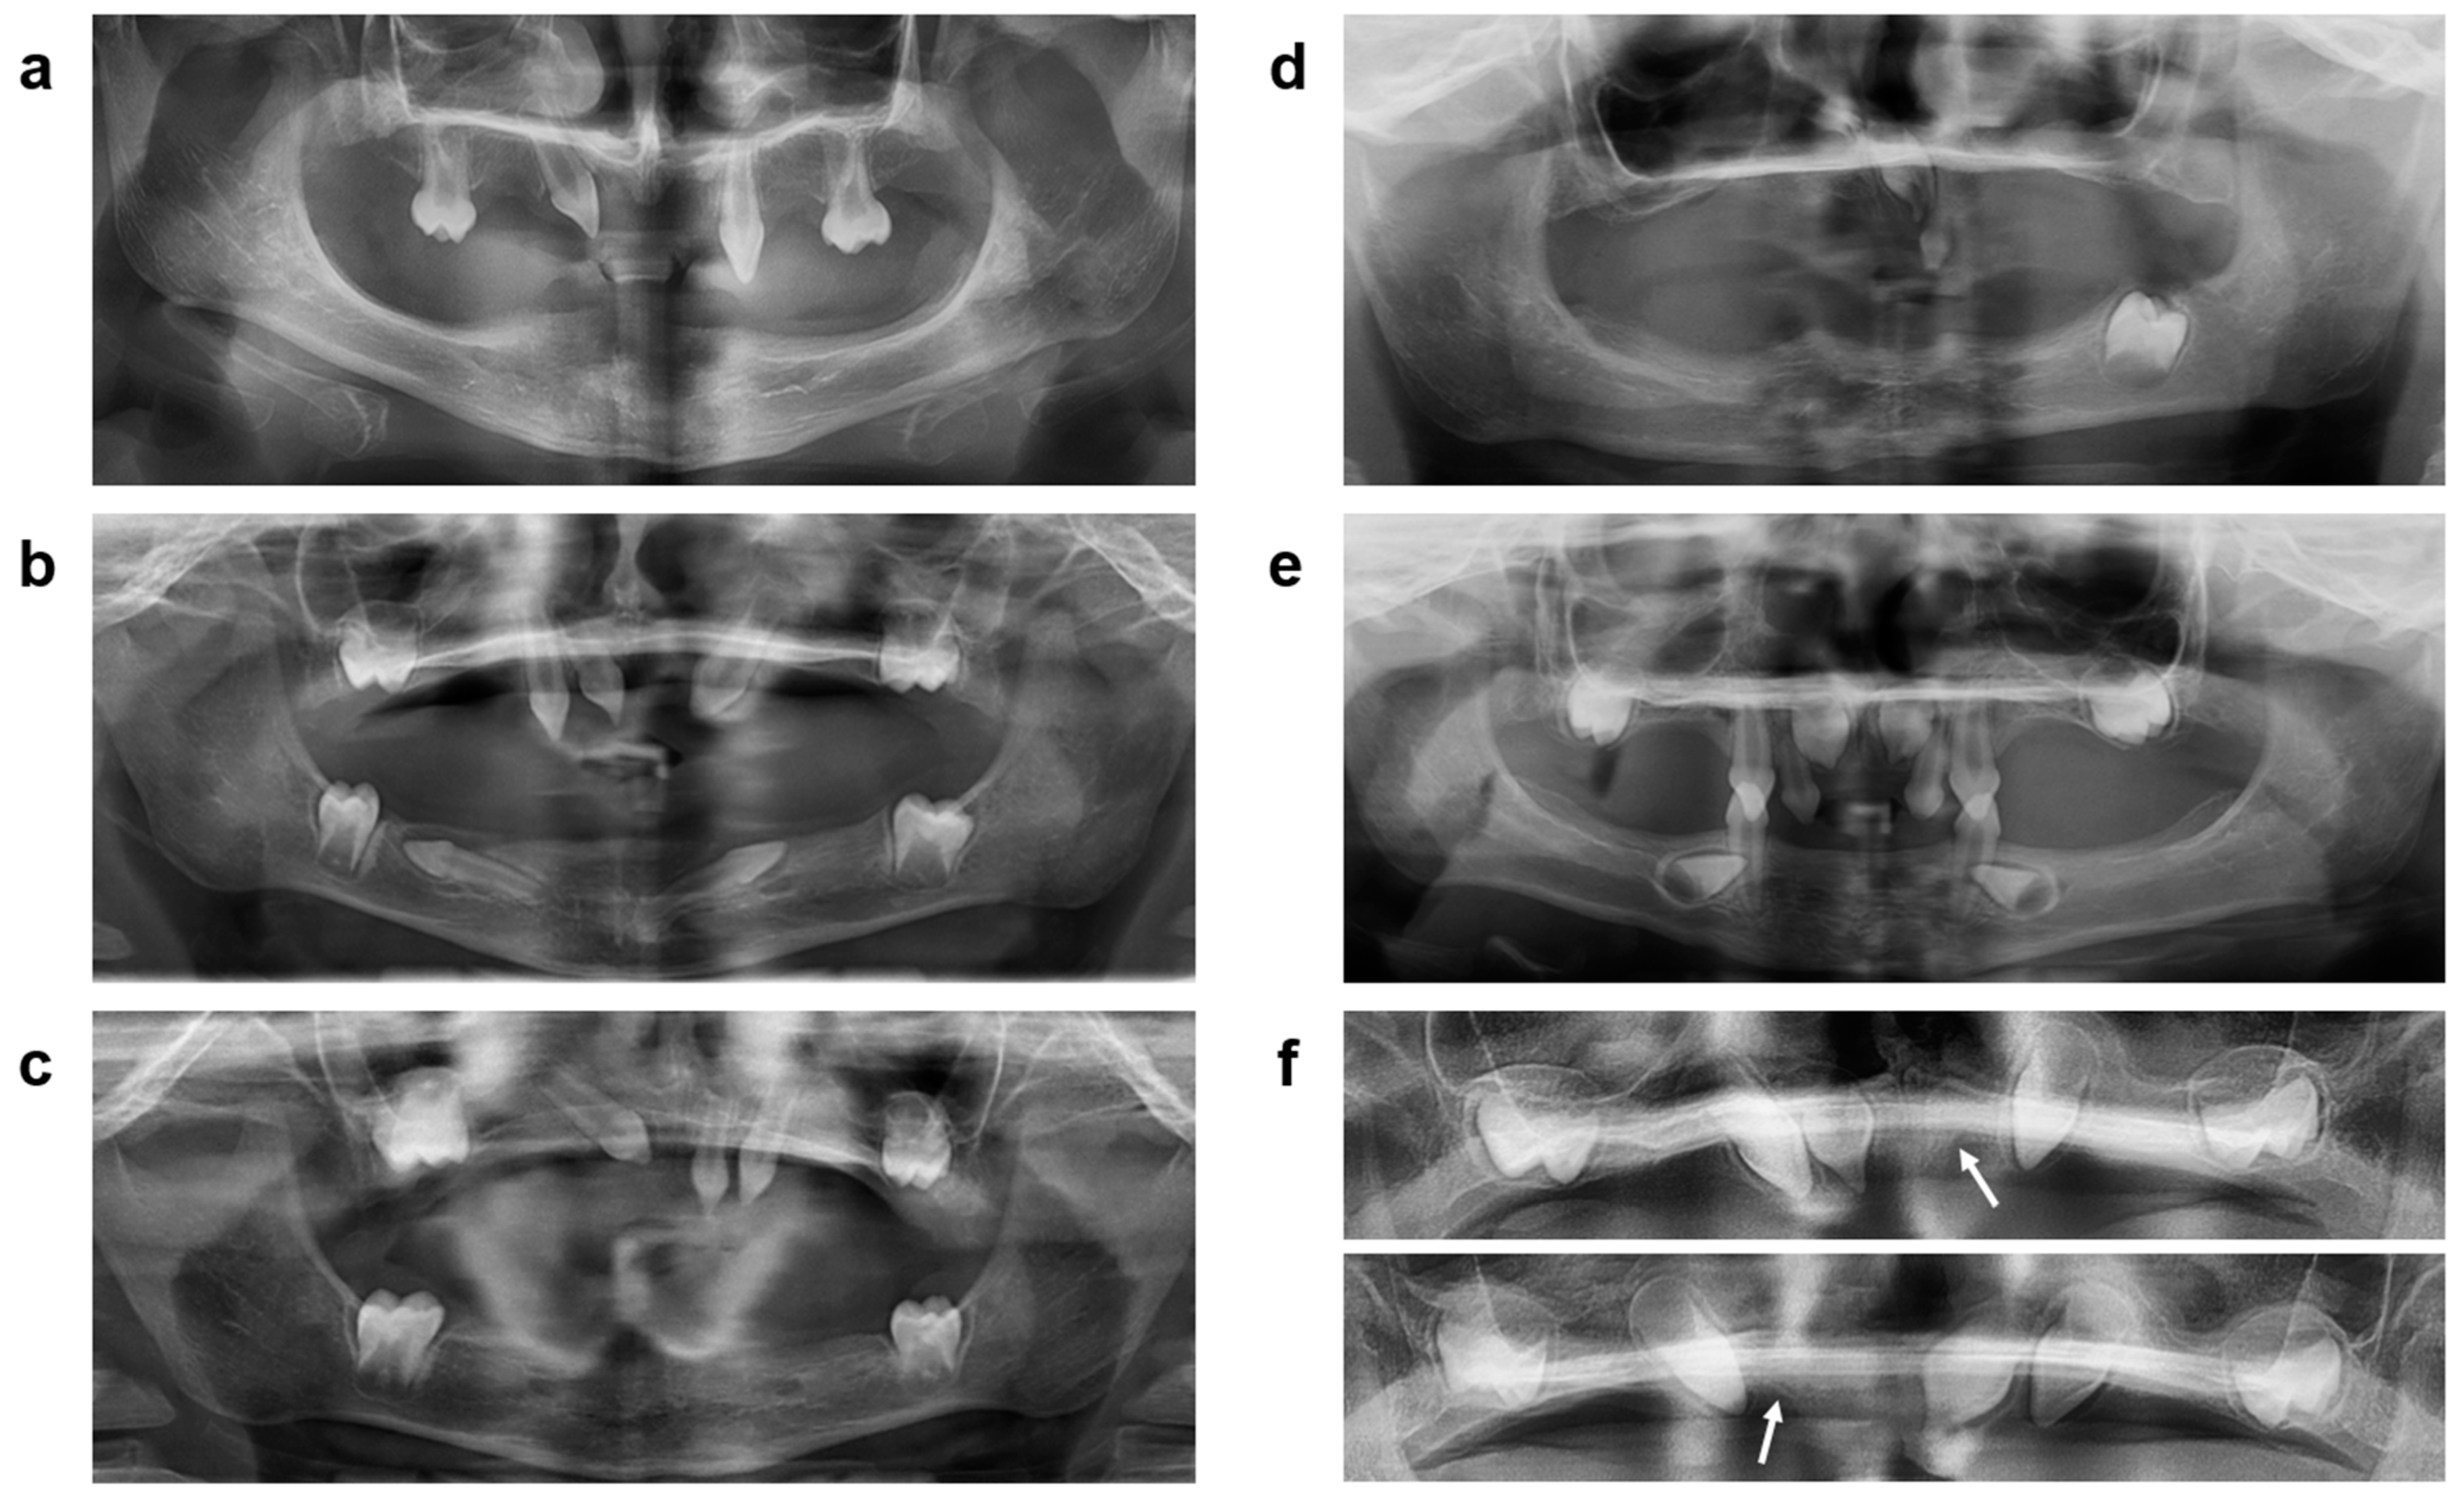

| Subject |

Body Length (cm) 1 | Body Weight (kg) 1 | Primary Teeth (Number) | Permanent Teeth (Number) | Pilocarpine- Induced Sweating (µL/30 min) | Episodes of Hyperthermia during the Summer? | Dry Eye Issues? | Nosebleeds (Number per Year) | Repeated Airway Infections? | Dry Mouth? | Hoarse Voice? | Dry Skin? |

|---|---|---|---|---|---|---|---|---|---|---|---|---|

| N1 | 106.5 14th perc. | 18.7 42nd perc. | 2 | 4 | 0 | yes | yes | 5 | yes | yes | yes | yes |

| N2 | 109 26th perc. | 17.6 24th perc. | 8 | 5 | 0 | yes | yes | 50 | yes | yes | yes | yes |

| N3 | 110 40th perc. | 18.7 44th perc. | 1 | 2 | 0 | yes | yes | 4 | yes | yes | yes | yes |

| P3 (single dose) | 108 41st perc. | 18.8 56th perc. | 4 | 8 | 7 | no | no | 2 | no | no | no | yes |

| P1 (two doses) | 105 10th perc. | 16.2 11th perc. | 1 | 9 | 41 | no | no | 0 | no | no | no | no |

| P2 (two doses) | 106 14th perc. | 16.5 14th perc. | 1 | 7 | 50 | no | no | 0 | no | no | no | no |